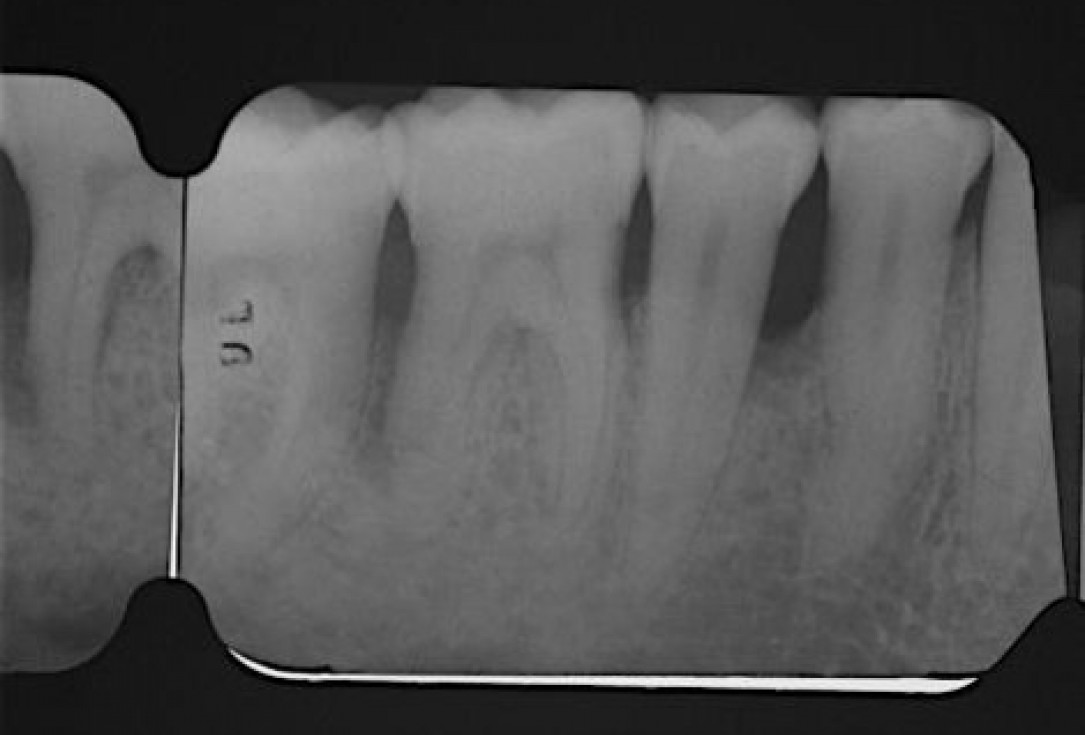

Radiographic view before periodontal regenerative therapy with Straumann® Emdogain®. A deep intrabony defect appeared mesially and distally on the left mandibular first premolar. Pre-surgical probing measured 8 mm. The defect morphology presented as well-contained.